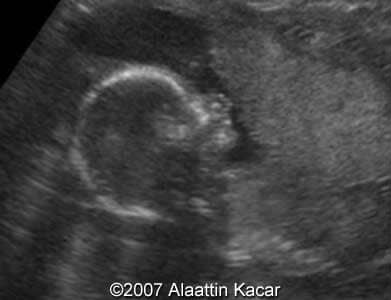

Cleft lip, bilateral Alaattin Kacar, MD Ahmet Celik, MD Merter Keceli,MD. Article Published: Jun 21, 2007 Balikesir, Turkey. These are some images demonstrating bilateral cleft lip of the fetus obtained at 17 weeks of pregnancy. Images 1, 2: Axial images at the level of the upper lip showing bilateral clefts within the upper lip. Images 1, 2: Parasagittal and sagittal images of the fetal head. Parasagittal image shows cleft at the level of the upper lip. Â Â Discussion Board Start a discussion about this article Add to Favorites Favorite